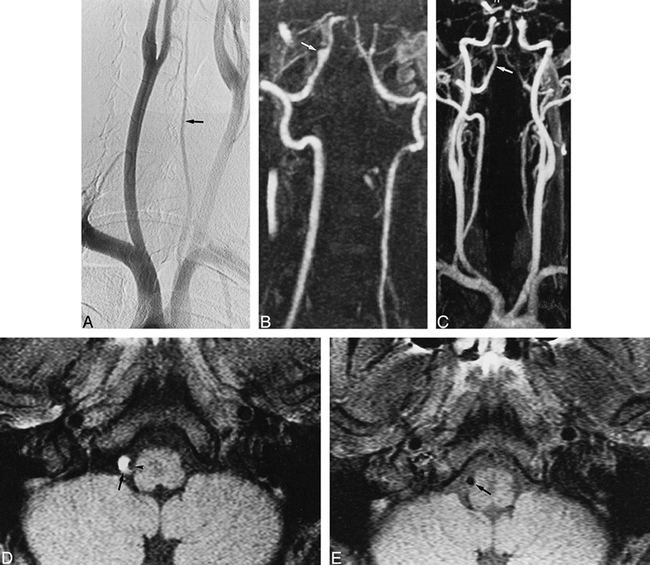

A 48-year-old man with occipital headaches, neck pain, and Wallenberg's syndrome.

A, Selective angiogram of the left VA shows typical aspect of stenotic dissection with a long stenosis (arrows) involving the V3 and V4 segments of the VA.

B, Early follow-up conventional angiogram, obtained at 4 months, shows a normal left VA (arrow) with complete resolution of luminal abnormalities.

C, Contrast-enhanced MR angiogram, obtained 29 months later, shows normal appearance of the left VA (arrow).